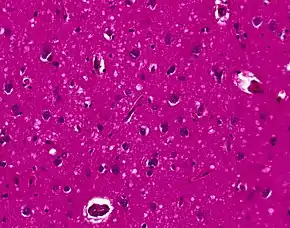

Spongiform change in CJD

Testing of tissue remains the most definitive way of confirming the diagnosis of CJD, although it must be recognized that even biopsy is not always conclusive.[51]

In one-third of people with sporadic CJD, deposits of "prion protein (scrapie)", PrPSc, can be found in the skeletal muscle and/or the spleen.[52] Diagnosis of vCJD can be supported by biopsy of the tonsils, which harbor significant amounts of PrPSc; however, biopsy of brain tissue is the definitive diagnostic test for all other forms of prion disease. Due to its invasiveness, biopsy will not be done if clinical suspicion is sufficiently high or low. A negative biopsy does not rule out CJD, since it may predominate in a specific part of the brain.[53]

The classic histologic appearance is spongiform change in the gray matter: the presence of many round vacuoles from one to 50 micrometers in the neuropil, in all six cortical layers in the cerebral cortex or with diffuse involvement of the cerebellar molecular layer.[54] These vacuoles appear glassy or eosinophilic and may coalesce. Neuronal loss and gliosis are also seen.[55] Plaques of amyloid-like material can be seen in the neocortex in some cases of CJD.[56]

However, extra-neuronal vacuolization can also be seen in other disease states. Diffuse cortical vacuolization occurs in Alzheimer's disease, and superficial cortical vacuolization occurs in ischemia and frontotemporal dementia. These vacuoles appear clear and punched-out. Larger vacuoles encircling neurons, vessels, and glia are a possible processing artifact.[53]